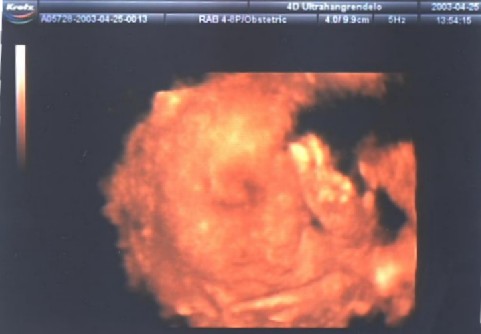

A két következő már háromdimenziós technikával készült. Ez valami újfajta nyavalya, még én sem értem teljesen. De azért integetek nektek egy jót!

Azt mondta a kedves doktor néni aki kezelte ezt a bonyolult berendezést, hogy apura fogok hasonlítani, talán a hörcsögpofim miatt. Hát én ezt nem tudom még, döntsd el inkább Te!